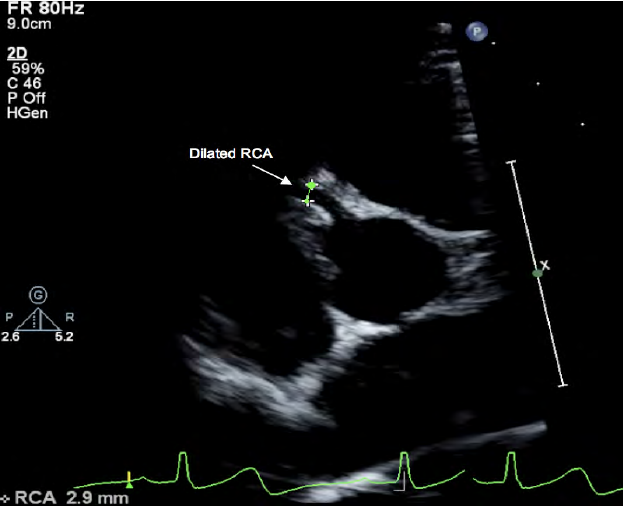

Right main coronary artery

What artery is seen in this image?